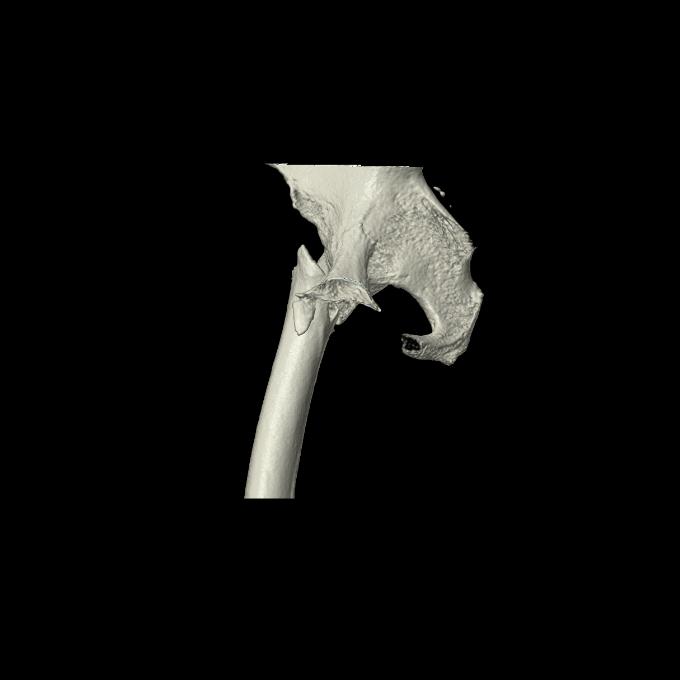

46666 1/28 両股正面+軸と 1/26 右手関節 2R 76歳女性 右転子部骨折